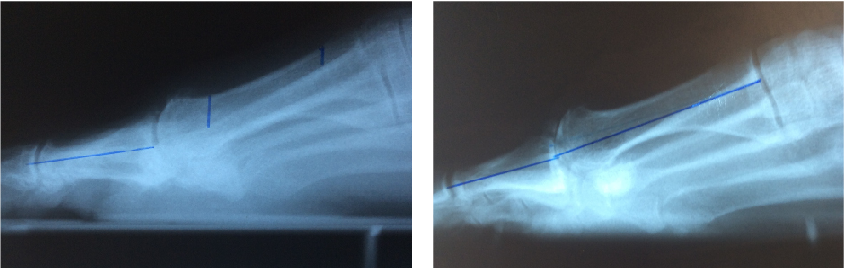

Metatarsu

s primus elevatus is basically a radiographic finding that theoretically depicts the position of the first metatarsal relative to the lesser metatarsals at the midstance phase of the gait cycle.18 In metatarsus primus elevatus, the first metatarsal is elevated to an abnormal position. However, there is no agreement as to the degree that this elevation is truly “abnormal” or pathologic. Some authors have noted that metatarsus primus elevatus can be present in normal, healthy feet with no evidence of hallux rigidus.19

Many authors have connected metatarsus primus elevatus as a causative factor for hallux rigidus. Meyer reviewed radiographs of 120 patients and found that hallux rigidus findings did correlate with the presence of metatarsus primus elevatus.20 Roukis determined the mean first to second metatarsal elevation to be 5.8 mm in a hallux rigidus group, which was higher than in patients with other foot pathologies.21 Bouaicha and coworkers attempted to standardize techniques to measure alignment of the first metatarsal on lateral radiographs and found that elevation of the first metatarsal greater than 5 mm was predictive of hallux rigidus.17

The fact that hallux rigidus and metatarsus primus elevatus seem to go together when looking at lateral radiographs reaffirmed the long held notion that hypermobility and elevation of the first ray must be a primary cause of hallux rigidus. However, two studies have raised the question about whether such a cause-effect relationship really exists. Horton and coworkers studied radiographs of patients with and without hallux rigidus, and found no difference in alignment of the first ray between the two groups.18 In cases of severe hallux rigidus, the metatarsus primus elevatus increased significantly, suggesting to the authors that elevation of the first metatarsal occurs as a result of hallux rigidus and not vice versa.

Bouaicha and coworkers further studied the role of metatarsus primus elevatus and hallux rigidus.17 They observed that some of the conflicting results of previous studies of metatarsus primus elevatus were due to unreliable measurement techniques of radiographs taken of patients with hallux rigidus. Bouaicha and colleagues described a new measurement technique to measure elevation of the first metatarsal relative to the second metatarsal. With this technique, a correlation between metatarsus primus elevatus and hallux rigidus was present, but the authors could not determine the cause-effect relationship.

However, a more interesting finding was reported in the Bouaicha study regarding the position of the hallux relative to the first metatarsal.17 This angular relationship in the sagittal plane, described as the first metatarsal dorsiflexion angle, showed a significant reduction (i.e. plantarflexion) in patients with hallux rigidus. Furthermore, there was a significant correlation with plantarflexion of the hallux and elevation of the first metatarsal in patients with hallux rigidus. The authors speculated that tensioning of the flexor hallucis longus tendon could be responsible for retrograde metatarsus primus elevatus.